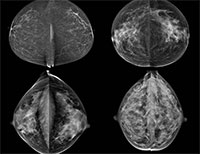

Prior research has shown an association between breast density and breast cancer. In addition, cancers in dense breast tissue are more difficult to see on mammograms. As a result, some women with dense breasts are advised to get supplementary screening with ultrasound or MRI. Some U.S. states have enacted legislation mandating breast density reporting to women undergoing mammography.

Two radiologists read the mammograms independently and determined breast density according to standard criteria. The researchers compared data between patients in the low-density breast tissue group and the high-density group.

The majority of screened woman had low breast density. Of the 230 detected breast cancers, almost half were from the group with the lowest ranked breast density, while slightly less than 3 percent came from women in the highest breast density category.

When the researchers matched the women who had a detected cancer with control participants of the same age and from the same locales who did not have cancer, they found no significant difference in mammographic density. Women with low mammographic density made up 83 percent of the patients in the breast cancer group, compared with 89 percent in the control group, while high mammographic density was found in 17 percent of the breast cancer patients and 11 percent of women in the control group.